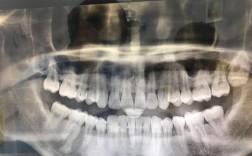

现代牙齿矫正已从传统“钢牙”发展到多种技术,如隐形矫正(时代天使、隐适美)、自锁托槽矫正、舌侧矫正等,优质机构通常会配备先进的数字化设备,如口内扫描仪(替代传统取模,提升舒适度)、3D数字化方案设计系统(可提前预知矫正效果)、CBCT(用于复杂病例的骨性分析),这些技术能提高矫正精度和效率。

- 关注案例效果:要求查看医生过往的矫正案例,尤其是与自己情况相似的案例,观察矫正后的牙齿排列、面部改善效果,这能直观反映医生的技术水平。